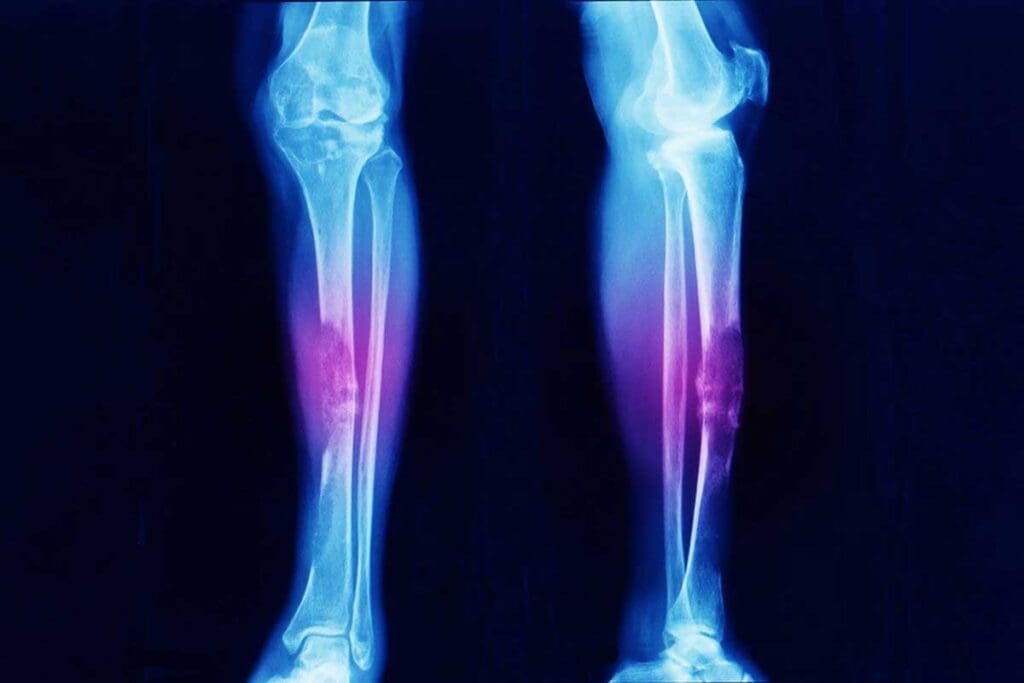

Common Locations Where Ewing Sarcoma Develops

Knowing where Ewing sarcoma usually starts is key for catching it early and treating it well. It can pop up in different parts of the body, with some spots being more common than others.

Primary Bone Sites

Ewing sarcoma often starts in the bones of the legs, pelvis, and chest wall. The long bones in the legs, like the femur and tibia, are very common. The pelvis is also a frequent spot, but it’s harder to treat because it’s deep inside.

Imaging Studies: X-rays, MRI, CT, and PET Scans

Imaging studies are vital in diagnosing Ewing sarcoma. Different imaging methods help see the tumor and its size.

• X-rays: Show bone abnormalities.

• MRI (Magnetic Resonance Imaging): Gives detailed images of soft tissues and the tumor’s extent.

• CT (Computed Tomography) Scans: Evaluate the tumor’s size and its effect on nearby structures.

• PET (Positron Emission Tomography) Scans: Detect metastasis and the tumor’s metabolic activity.